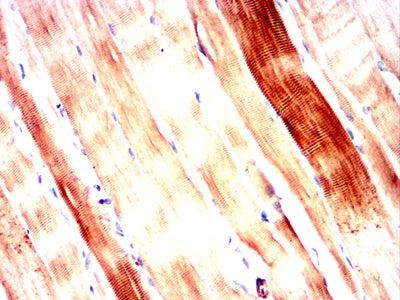

Immunohistochemical analysis of paraffin-embedded Rat myocardium tissues using ATM mouse mAb with DAB staining.

-